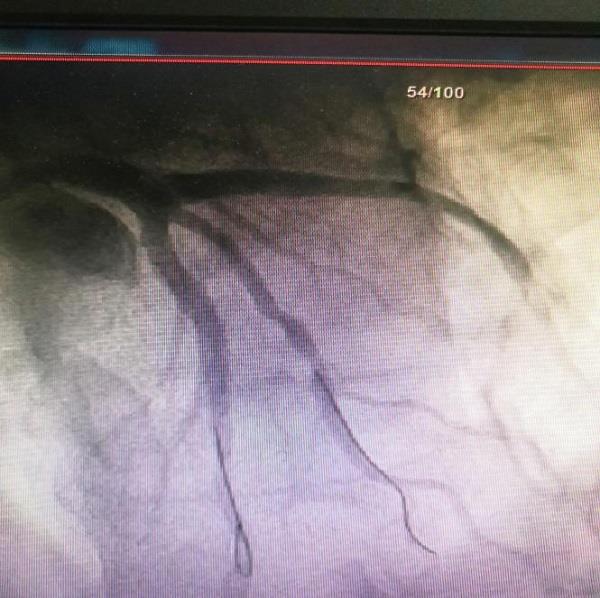

科室治疗组详细询问胡先生病情并组织讨论,制定治疗方案、完善术前检查后,心血管内科介入手术团队对胡先生行冠脉造影检查,结果证实冠状动脉前降支钙化伴重度狭窄(85%以上狭窄),并影响远端血流流速,粗大对角支近段狭窄80%。在胡先生和家属同意下,介入手术团队在前降支成功植入1枚支架后,血管狭窄消失,对角支狭窄处给予冠状动脉药物球囊治疗,血管狭窄明显减轻,病变血流恢复正常,胡先生胸痛胸闷症状得以缓解。手术后,胡先生身体健康状况恢复良好,家人感激不已,随送来一面锦旗以表谢意。

治疗后,前降支和对角支狭窄明显改善